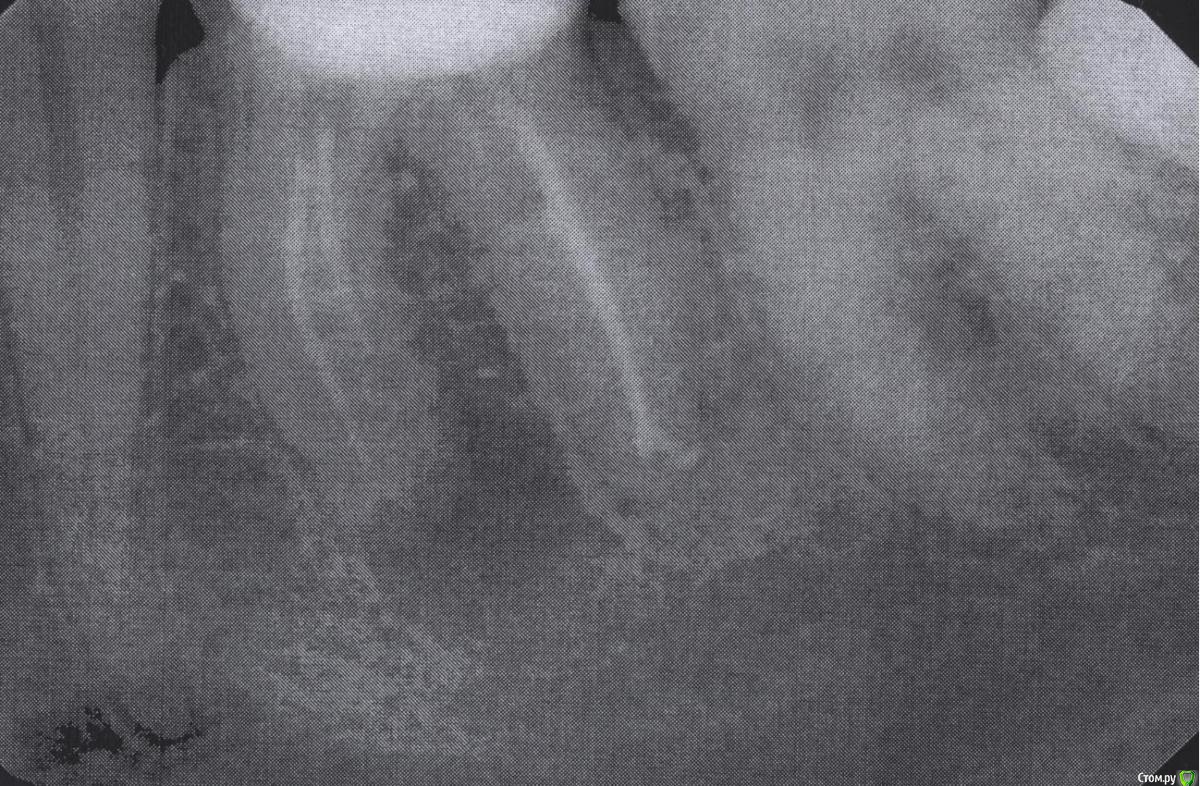

ClayMixer Опубликовано 18 ноября, 2016 Поделиться Опубликовано 18 ноября, 2016 (изменено) Здравствуйте! Вопросы по двум зубам (36 и 26): 1. Киста (36-ой зуб).Консультировалась у нескольких врачей. Мнения разные. От "можно поставить вкладку и коронку на n-ное количество времени до удаления; эту кисту не вылечить", до: "только удаление, желательно быстрее". 1) Можно ли вылечить этот зуб? И каков процент успеха?2) Есть ли смысл лечить зуб и ставить вкладку и коронку или лучше удалить и делать имплант? После того, как 36 зуб подготовили под вкладку - бывали неприятные непонятные ощущения (похожие на импульсы), не острые (длительностью 3 нед.) Вроде после этого времени стали утихать понемногу. 2. Инородное тело (обломок инструмента) в 26-м зубе.Врачи пытались извлечь его (без микроскопа) - безуспешно. Канал, в котором "застрял" инструмент не до конца "пройден".Критично ли это? Какова вероятность воспаления? (теперь патологический страх появления кисты ) Теоретически можно ставить вкладку и коронку? Ходила таким трансформером больше 5-ти лет, не беспокоил вообще. После попыток врачей достать инструмент также бывали неприятные непонятные ощущения (похожие на импульсы), не острые (длительностью 3 нед.) Вроде после этого времени стали утихать. При простукивании коронки обеих зубов болевых ощущений вроде не наблюдалось. Результаты КТ https://cloud.mail.ru/public/Fhy4/ESmeyU9hp Изменено 18 ноября, 2016 пользователем ClayMixer Ссылка на комментарий

ClayMixer Опубликовано 18 ноября, 2016 Автор Поделиться Опубликовано 18 ноября, 2016 26-ой зуб Ссылка на комментарий